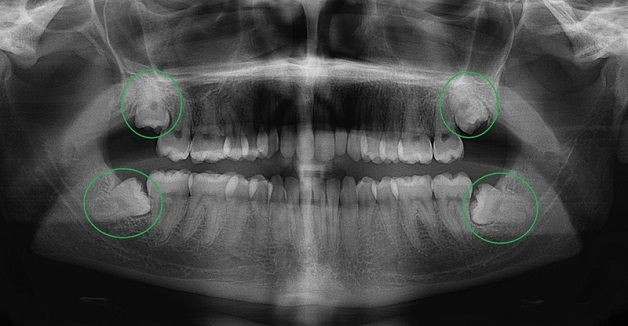

– Phát hiện tình trạng răng khôn mọc ngầm, mọc lệch bao nhiêu độ, răng khôn mọc ngang gây ảnh hưởng tới các răng ăn nhai bên cạnh ra sao.

– Chụp X quang cũng có thể giúp phát hiện tình trạng bị nhiễm trùng, u nang tại nướu hoặc hàm.

– Giúp ghi nhận những hình ảnh về kích thước răng, chân răng và hình dạng của răng khôn.

– Xác định được chiều dài tuỷ răng tại vị trí răng viêm nhiễm để điều trị tận gốc.